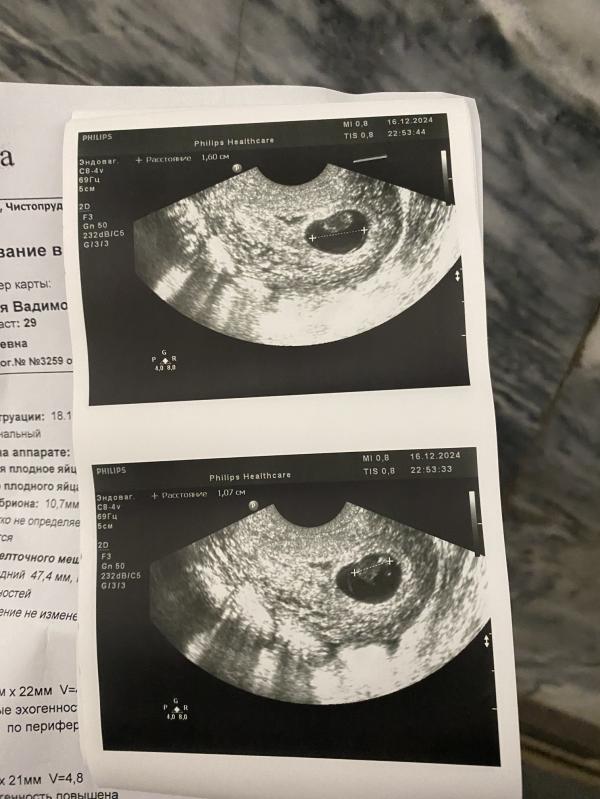

Была сегодня на узи сказали что сердцебиение непостоянное , мол плод развивается , желтое тело выросло все ок , но сердце якобы прослушивается плохо

Врач сказала обязательно перепроверить результат , тк диагноз не окончательный

Ктр соответствует диаметру ПЯ. Сколько у вас по месячным?

Что значит плохо прослушивается, это фигня какая то. Простите. Ставят кол-во ударов. А по ним уже судят плохо все или нет. Я не вижу, вам поставили какое сердцебиение?

@kulich45, у вас есть предыдущее узи? С чем сравнить. У меня было 3 зб, но ни разу не говорили, что плохо прослушивается. Сб было низкое.